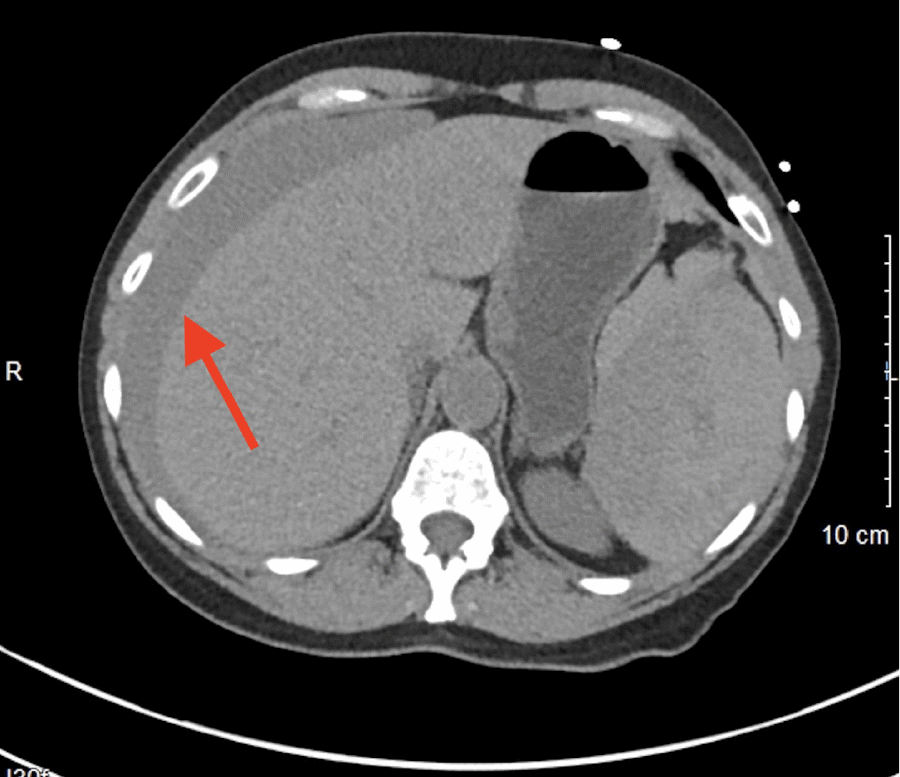

Initial hemoglobin and hematocrit were 9.2 g/dL and 27.5%, respectively, and the WBC was 22,200/mm3. Creatinine was 3.6 mg/dL, and BUN was measured at 44 mg/dL. No prior laboratory values were available for comparison. A non-contrast CT scan of the abdomen and pelvis was obtained due to elevated creatinine, which showed a grade IV splenic rupture according to the American Association for the Surgery of Trauma (AAST) splenic injury scale. The parenchymal hematoma was reported to be 12 × 15 cm with a large halo of blood around the liver (Figure 1). A moderate amount of blood was also evident in the pelvis (Figure 2). Operative management was pursued versus nonoperative means due to the grade of the splenic rupture and the amount of blood in the abdomen.

Figure 1. CT Image Demonstrating Grade IV Splenic Rupture. Published with Permission

12 × 15 cm parenchymal hematoma with large halo of blood around liver (arrow).